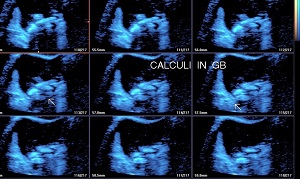

• Solitary Calculi:

• Multiple Calculi